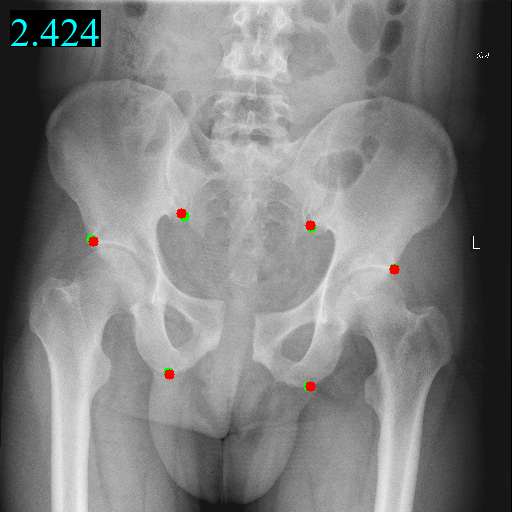

Figure 2: Visualization examples of guidance heatmap Y~gsubscript~𝑌𝑔\tilde{Y}_{g}, fine heatmap Y~fsubscript~𝑌𝑓\tilde{Y}_{f}, output heatmap Y~~𝑌\tilde{Y} and images along with landmarks from four domains on head, hand, chest, and pelvis. The red points \bullet are predicted landmarks while the green points \bullet are annotated landmarks. The MRE value is on the top left corner of the image.

Transferring to a novel domain Furthermore, to demonstrate the effectiveness of new domain adaption, we finetune the trained DATR and corresponding basic transformer model on a new in-house pelvis dataset by freezing domain-shared parameters and adding domain-specific parameters in parallel. As Table  4 shows, our domain-specific transformer performs better than basic transformer, which indicates our proposed DATR learns shared common knowledge to boost the performance of each domain. The landmarks are visualized in Figure 2.

Table 4: Quantitative results of domain adaption on a new pelvis dataset, including 6 landmarks, 100 training images and 36 test images.

Model MRE (px) SDR<3px(%) SDR <6px(%) SDR <9px(%)

Basic transformer 5.64 41.97 76.17 85.82

Domain-adaptive transformer 4.12 48.30 81.82 90.91